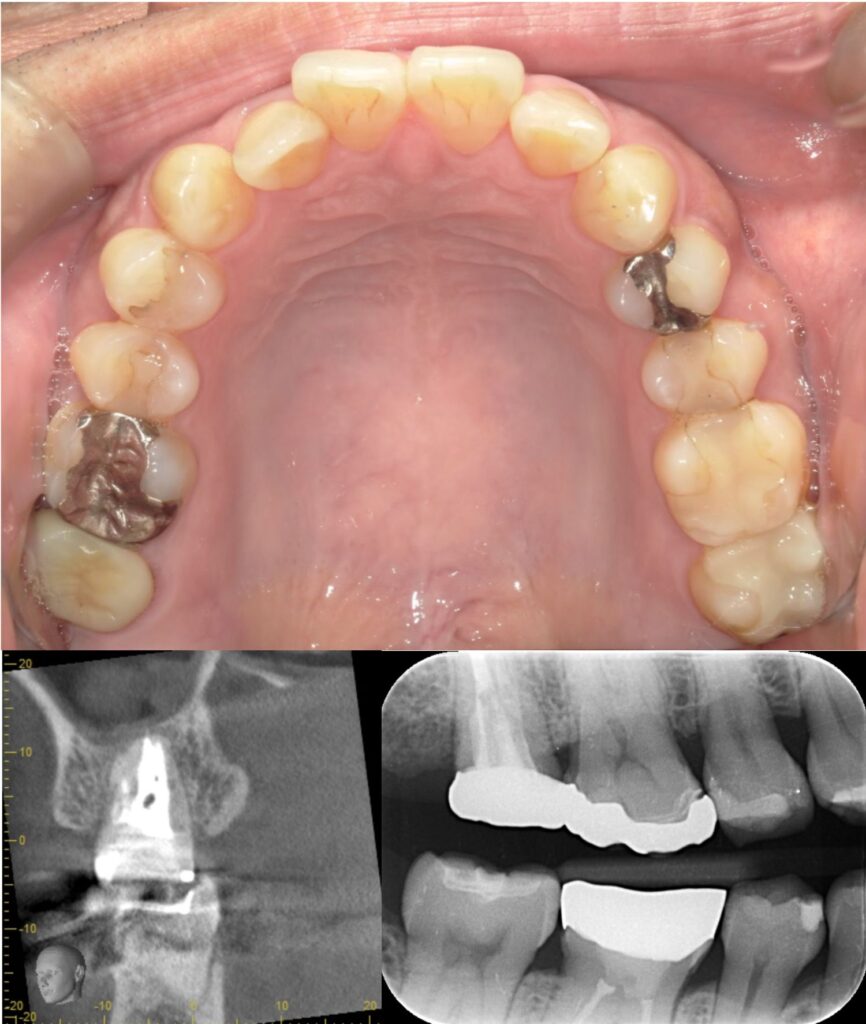

歯と歯の間のう蝕の為肉眼では分かりにくく、気づいた時には歯髄に近接し、保険治療では抜髄(神経を除くこと)になってしまうケースが多い。そのため処置前に、十分な精査と、患者さんが神経を残したいという希望の有無をしっかり相談・説明することが重要と考えています。

| 診断 | ①右上7根尖性歯周炎 ②重度う蝕 ③左上7歯髄に近接するステージ3のう蝕 |

| 処置内容 (または主訴) | ①マイクロスコープによる根管治療 ②マイクロスコープによるう蝕除去およびセラミック修復 ③MTAを用いたマイクロスコープによる歯髄温存療法からセレック修復 |